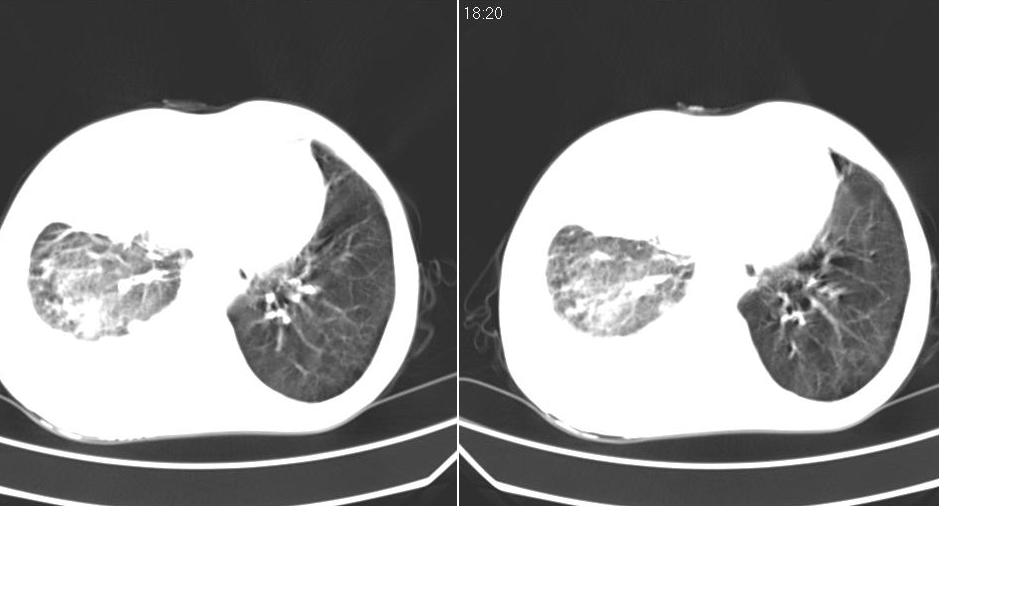

以下是引用zsl6918在2008-5-3 19:53:00的发言:[br]右肺中心型肺癌并纵隔淋巴结转移,胸膜转移,右肺癌性淋巴管炎。

以下是引用liuyue在2008-5-3 20:49:00的发言:[br]1.右侧中心型肺癌伴双肺转移瘤、纵隔淋巴结转移、右侧胸腔积液(侵及胸膜所致可能性大)。[br]2.右肺阻塞性肺炎,癌性淋巴管炎不除外。